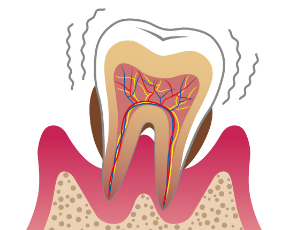

C3:歯の中の神経にまでおよんだむし歯

症状

象牙質の内側の歯の神経にまで汚染が進んだ状態です。何もしなくてもズキズキ痛みます。

主な治療法

できるだけ歯残すために、神経や血管を取り除いて薬剤をすき間なく詰める「根管治療(こんかんちりょう)」を行い、被せ物で歯の機能を補います。